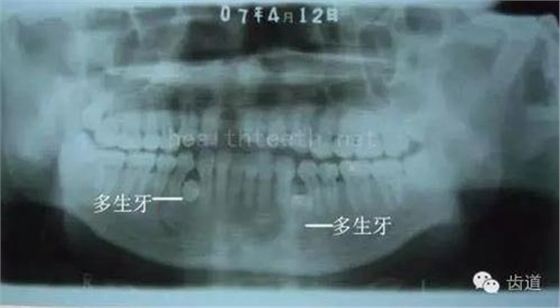

長期戴活動義齒不當或是戴不良修復(fù)義齒造成的口腔粘膜潰瘍,應(yīng)該引起高度警惕,因為這種潰瘍?nèi)菀装┳?/span> 黑毛舌 舌息肉,該患者同時伴有胃、食管息肉,后來看內(nèi)科了,具體情況不詳 四、孩子的牙齒問題 乳牙未退,牙根穿出牙齦對上唇粘膜造成刺激 乳牙滯留,也是孩子在退牙過程中最容易遇到的問題 五、牙齒發(fā)育上的問題 變色牙 氟斑牙 釉質(zhì)發(fā)育不全 四環(huán)素牙 牙神經(jīng)治療后的牙齒變色 10歲孩子剛剛萌出的牙齒變色 2、埋伏牙 左上乳3滯留,恒3未見萌出,曲面斷層片顯示牙齒埋伏 通過CT片確定埋伏牙齒具體的位置,顯示距離左側(cè)上頜竇很近,偏唇側(cè),這為手術(shù)定位提供了方便 手術(shù)中切斷、完整拔出,未損傷上頜竇 其他埋伏牙 3、多生牙 病例1 病例2 病例3,同時多生兩顆牙齒 4、各種畸形牙 畸形過小牙 融合牙:恒牙和乳牙都可以發(fā)生融合的情況(兩顆牙齒長在了一起) 畸形中央尖:在牙齒的中央,兩個牙尖之間又多長出一個牙尖,由于進食的磨耗很容易造成磨穿,神經(jīng)就會與外界相通,出現(xiàn)牙髓炎的癥狀 六、牙齒的外傷 牙冠折斷 牙根折斷 烤瓷牙打樁修復(fù)后牙根折斷 外傷后牙齒的全脫位,應(yīng)該保留牙齒盡早做再植手術(shù) 七、牙齒的慢性損傷 牙頸部楔狀缺損 牙冠劈裂及完整拔除后的情況 牙根縱裂及拔除后的情況 牙隱裂,牙齒表面有肉眼看不到的裂紋,細菌通過其進入牙髓,容易出現(xiàn)牙髓炎癥狀,嚴重可以造成牙齒的劈裂 這是一位來中國學(xué)習(xí)的俄羅斯大學(xué)生的牙齒,已經(jīng)做過了根管治療,牙齒咬合面有隱裂,通過鋼絲結(jié)扎固定,做鑄造金屬冠修復(fù)。 八、牙髓炎、根尖周炎 下面圖片都是慢性根尖周炎的病例,有了齲齒,進一步發(fā)展就是牙髓炎,如果此時沒有得到及時的治療,疾病會逐漸發(fā)展破壞到根尖的骨質(zhì),將骨質(zhì)破壞后就在牙齦上出現(xiàn)一個膿瘺,此時患者不再感覺到牙齒的疼痛了,往往忽視了治療,但是這種不痛并不是疾病好轉(zhuǎn)了,而是因為疾病的炎性滲出得到了引流,這個膿瘺會出現(xiàn)有時候變大了,有時候又變小了,但是如果不治療是不會自己愈合的,只有經(jīng)過完善的根管治療后才有好轉(zhuǎn)的可能,但是在疾病的治療中時間是起決定作用的,時間拖得越晚,好轉(zhuǎn)的可能性越小,經(jīng)過根管治療后如果膿瘺還是沒有消失,就需要做根尖刮治術(shù),如果仍然沒有好轉(zhuǎn),就只能做根尖切除術(shù)了,這對牙齒的穩(wěn)固是不利的。下面圖片中在膿瘺中插入了一個牙膠尖,是我們做根管充填用的材料,是非常軟的,就是在口腔牙齦瘺管的地方插進去,通過拍牙片可以清晰地看到它到達的位置,從而確定發(fā)病的牙齒,此處是為了讓大家看得更清楚。 門牙兩個膿瘺 烤瓷牙修復(fù)后牙齦出現(xiàn)兩個膿瘺,插入牙膠尖,牙片顯示牙膠尖到達的位置就是根尖炎癥的位置,根尖骨質(zhì)密度降低(發(fā)黑的地方) 牙齒根尖膿瘺,治療前、中、后的圖片對照,完善根管治療后膿瘺明顯消失了 牙髓炎和根尖炎治療的關(guān)鍵就是根管治療 合格的根管充填治療 不良的根管充填治療 九、關(guān)于智齒(第八顆牙) 四顆長不出來的智齒 智齒反復(fù)發(fā)炎造成的頰瘺,膿腫切開引流后面部會留疤 智齒造成的頜骨囊腫,手術(shù)切除后需要植骨 十、各種錯合畸形 開合 深覆合 深覆蓋,上頜前突 反合(地包天) 牙齒排列擁擠 來源:牙醫(yī)愛看的 KQ88口腔醫(yī)學(xué)網(wǎng)